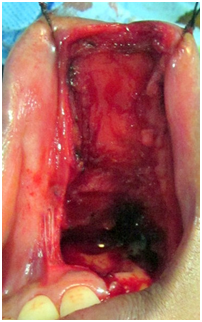

A 34year female patient reported to our department with complaints of recurrent swelling and mild discoloration of skin and upper lip mucosa. The discoloration was noticed for the past 1year and was not associated with pain. On clinical examination, extraorally mild swelling and discoloration of upper lip and skin was seen (Figure 1). The discoloration was also present on left inner side of mucosa of upper lip measuring around 2cmX1.5cm, extending from mucogingival junction upto vermillion border. Mild pulsations were felt on palpation and angiogram was done. Superior labial vessels were identified as the source of vascular supply and no other collaterals were present. Wide excision of the lesion was planned under GA (Figure 3). Superficial mucosa and muscular layer were excised along with the lesion by locally ligating the superior labial vessels (Figure 4-6). Intraoral mucosal flap were advanced for primary closure of the defect (Figure 7). Postoperative phase was uneventful, six month follow up shows no recurrence of the lesion (Figure 8).

Figure 4Ligation of the vessel and excision of the lesion.

Figure 5Surgical defect after excising the lesion.